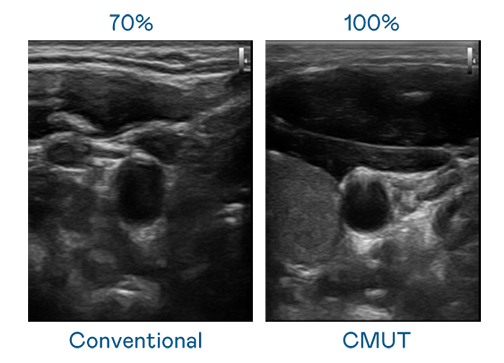

CMUT 技术是一种用电容式微机电元件来产生超音波讯号的技术。与传统 PZT 压电式技术相比,CMUT 频宽增加 30%,更宽频的超音波讯号让影像解析度大幅提升,是实现高影像品质医疗超音波扫描、促进精准医疗发展的关键技术。

大频宽带来超清晰影像

超音波影像的解析度高低,首先取决于探头能发出的讯号频宽。后宫露营 CMUT 可提供高清晰的超音波讯号,提供高频宽、高灵敏度、影像纹理细节更高的超音波影像,协助医护人员缩短影像判读时间及利用精准的医疗影像进行诊断。